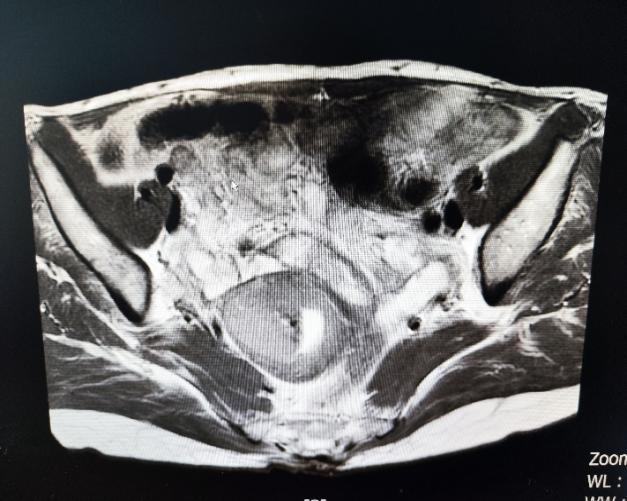

盆腔核磁:子宫内膜不均匀增厚并弥散受限,考虑子宫内膜癌(IB期)。全腹部增强CT、肿瘤标志物等未见进一步异常。